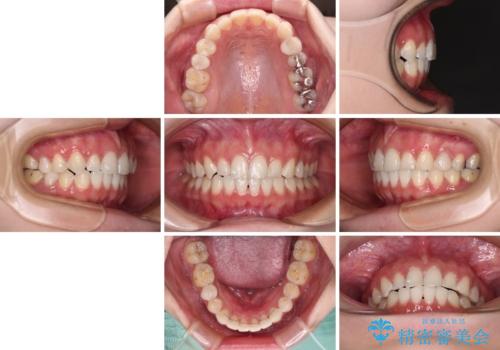

- 前歯の歯列不正を気にして来院された患者様です。

インビザラインでの矯正治療を希望されていましたが、奥歯の咬み合わせがインビザライン単独では改善困難と判断されたので、補助装置を併用することとしました。

まずは裏側の装置やワイヤー矯正を用いて歯列幅の狭い上顎を側方に拡大しつつ全体を後方に移動させ、その後インビザラインにて歯列を整えることとしました。